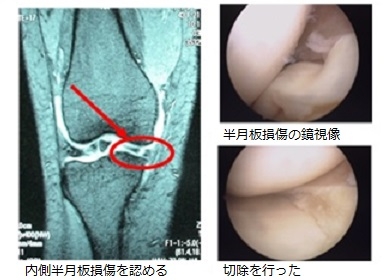

Amazon.co.jp: 肩関節鏡視下手術 (ビジュアル・サージカル。鏡視下バンカート修復術|森大祐(京都)。関節鏡・スポーツ整形外科センターのご紹介 | 診療科・診療。ベトナムチョコ LAVA 30枚入り。肩 脱臼 手術 | あんしん病院。関節鏡視下手術 ~肩、膝、スポーツ障害へのアプローチ~。腱板断裂に対する低侵襲手術 −関節鏡視下腱板修復を中心に。肩・肘の外科 - 大阪医科薬科大学整形外科学教室。肩関節センター | 整形外科 | 倉敷中央病院。関節鏡・スポーツ整形外科センターのご紹介 | 診療科・診療。主な肩関節鏡手術 | 肩関節鏡手術の職人 鈴木隆。関節鏡視下手術 | AR-Ex 尾山台整形外科。鏡視下肩関節唇形成術後にソフトテニスに復帰された患者様 | AR。「肩関節鏡視下手術」石橋 恭之 / 三幡 輝久定価: ¥ 16000 マーカー、書き込みありません裁断済みです